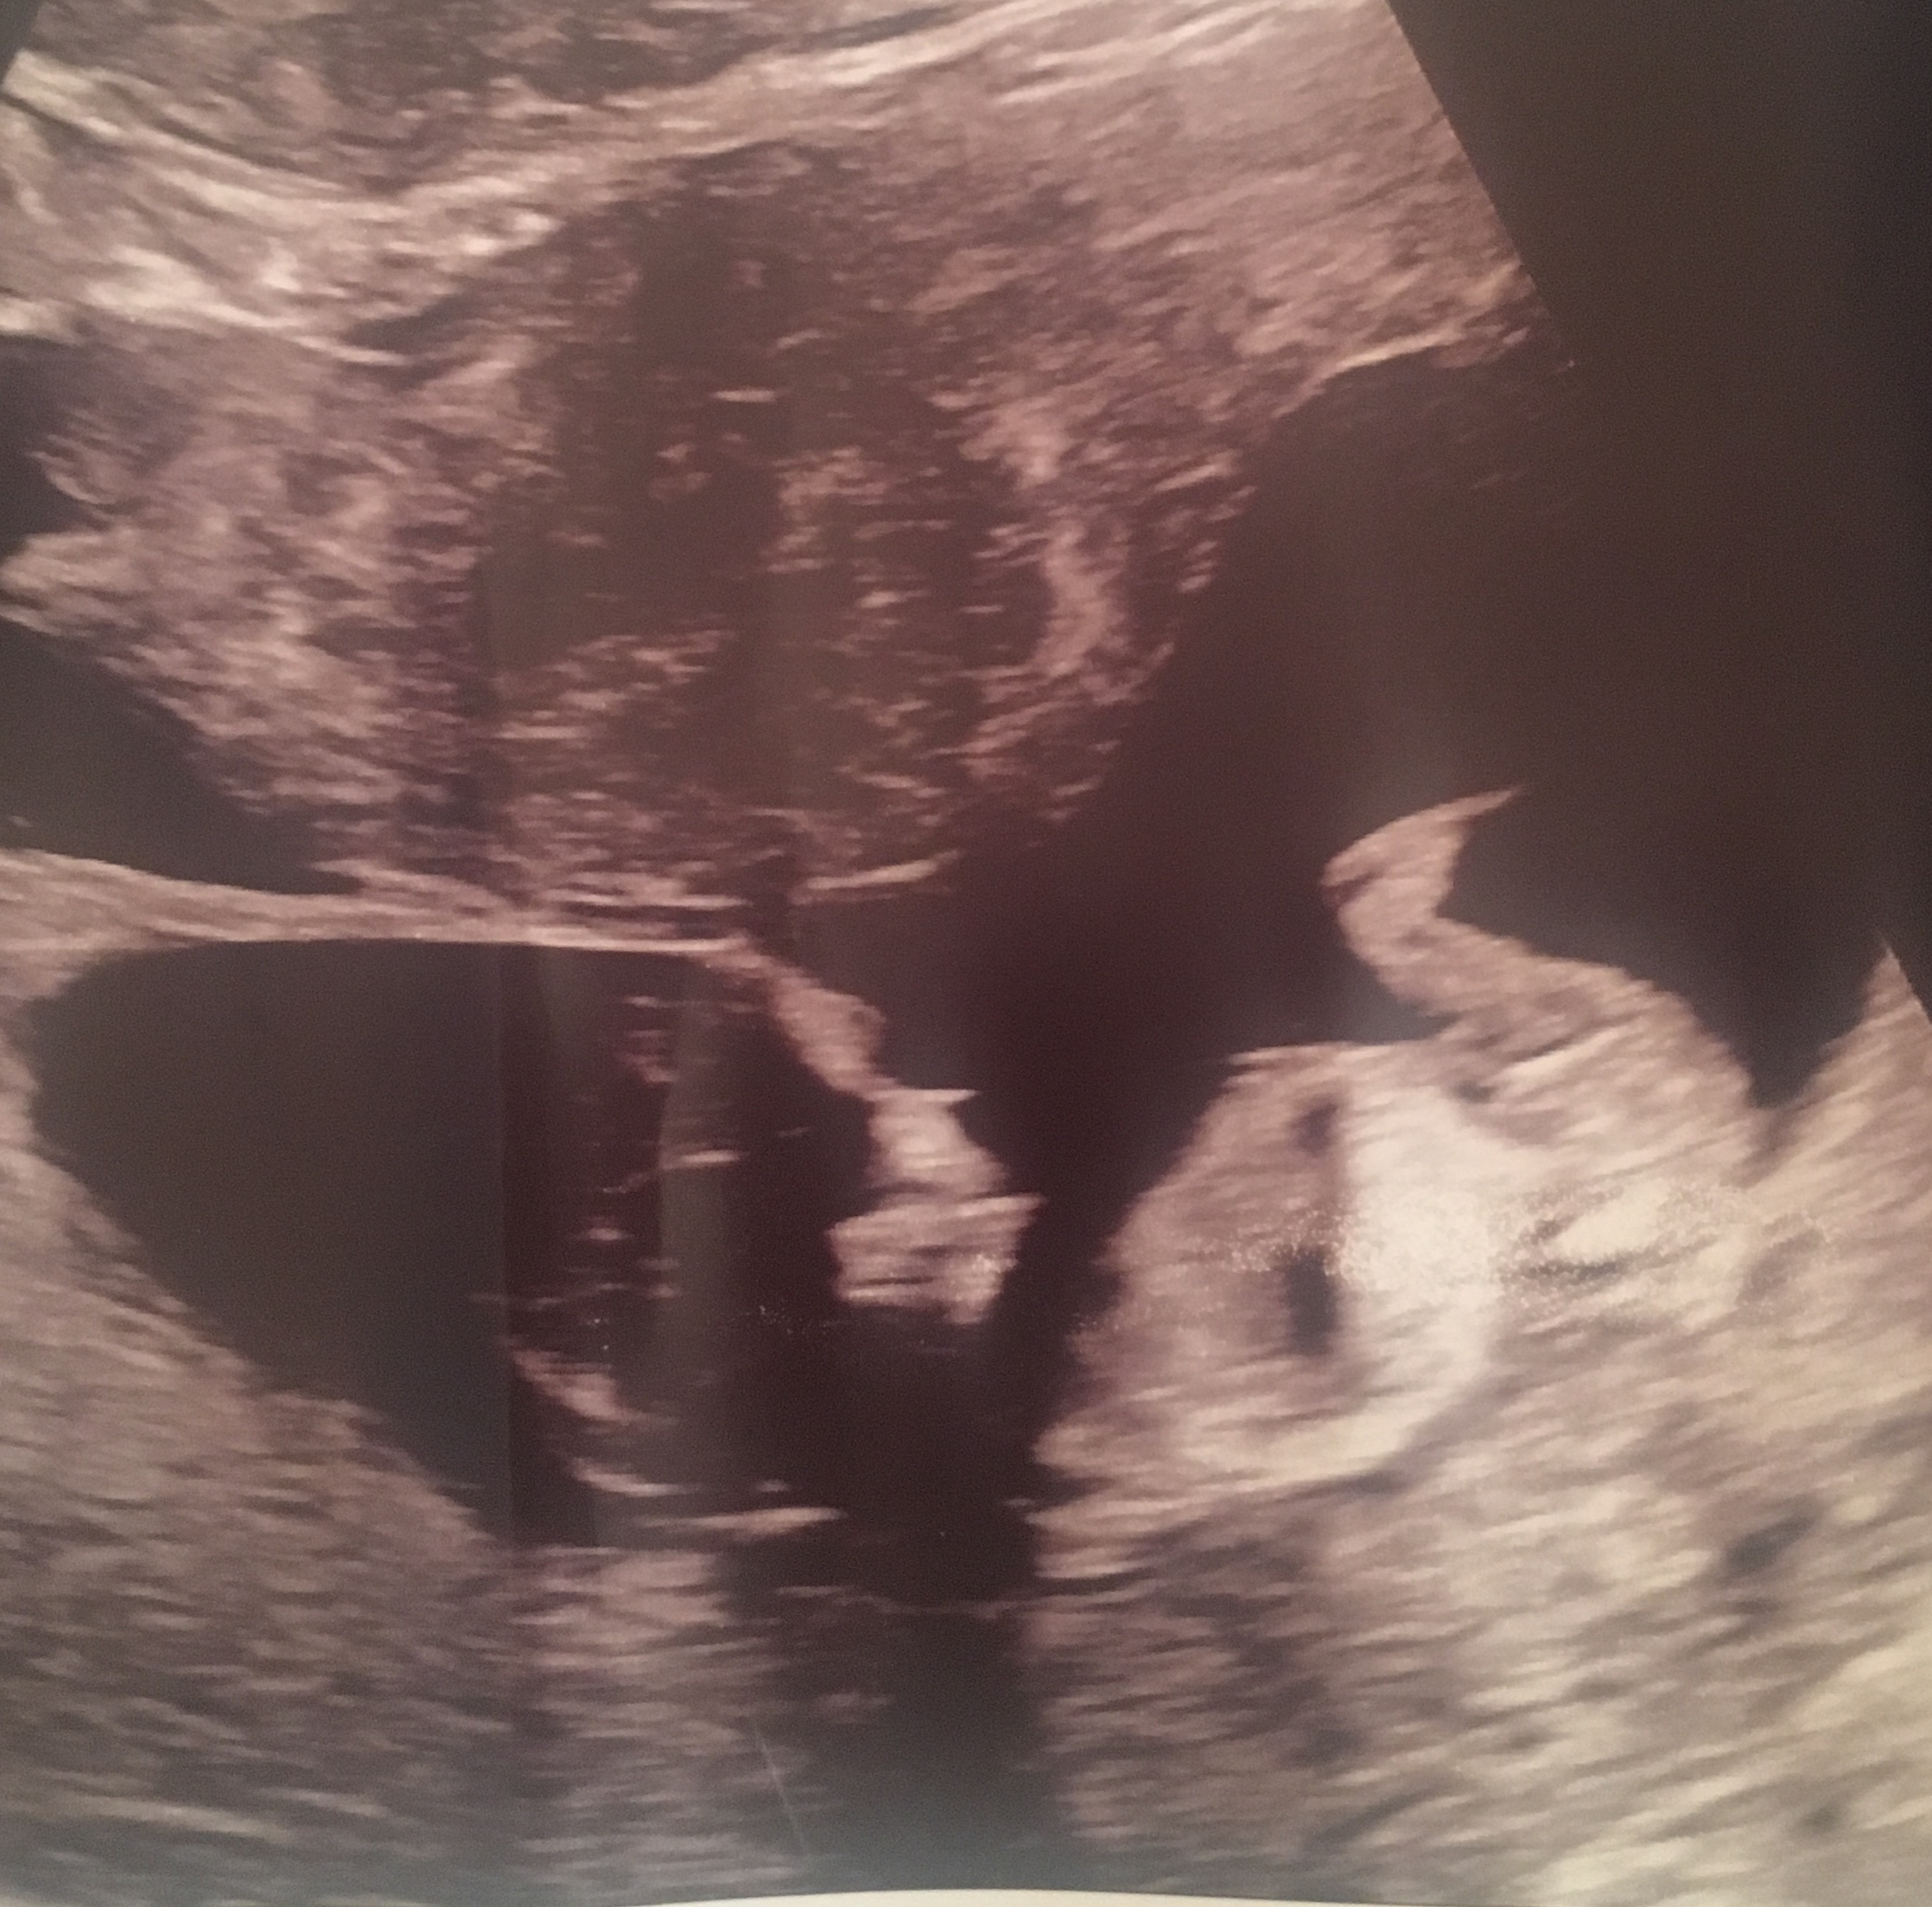

Nub! Boy or girl?!? :D